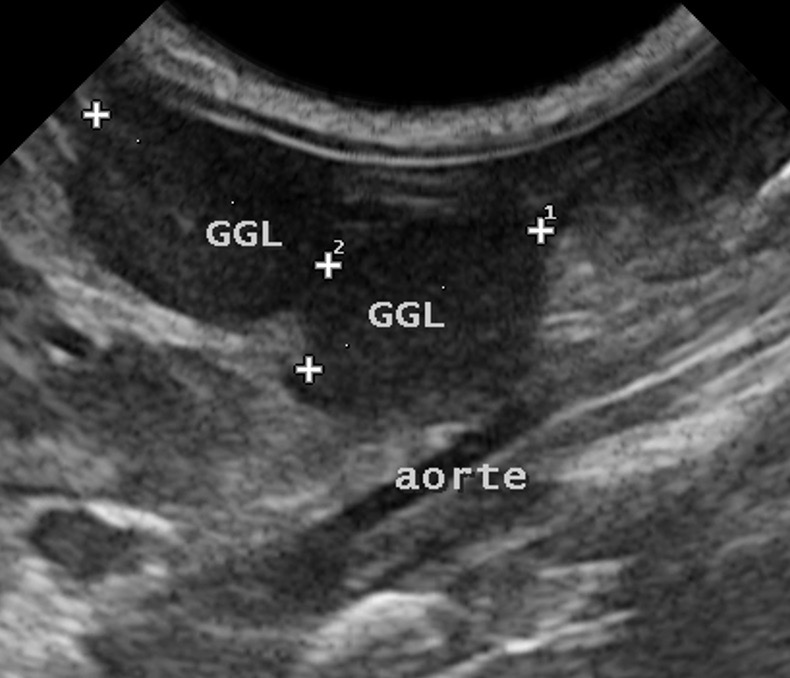

Pour progresser dans un diagnostic de PIF, l’échographie est nettement plus intéressante : côté abdomen surtout, elle permettra non seulement de confirmer (ou pas) la présence de liquide, même lorsque celui-ci est en faible quantité. Elle permettra aussi de voir, à travers ce liquide, l’aspect des organes abdominaux, et notamment les modifications dont on a parlé plus haut : hypertrophie des ganglions, déformations de la paroi intestinale, augmentation ou diminution de la taille des reins avec un éventuel anneau médullaire (on en a vu un exemple dans la partie « Symptômes »), modifications de la forme ou de la structure du foie, etc. Elle permettra enfin de réaliser des ponctions : en premier lieu pour aspirer du liquide d’ascite, (quand il y en a beaucoup, à la limite, on pourrait se passer d’échographie, mais quand il y en a peu, l’écho est indispensable), mais aussi pour ponctionner des organes suspects en vue d’analyses.

L’examen cytologique présente l’avantage de la simplicité (une ponction à l’aiguille, et un examen au microscope dans la foulée, après étalement et coloration), mais ne donne pas un diagnostic de certitude. Il permet malgré tout de se rendre compte si les cellules collectées sont compatibles avec l’hypothèse de PIF (réaction pyogranulomateuse au milieu des cellules normales de l’organe ponctionné), et d’éliminer d’autres hypothèses (par exemple, un lymphome… surtout si c’est un gros ganglion que l’on a ponctionné). Les publications semblent montrer que ça marche bien pour les cytoponctions de ganglions, (Green, 2023), un peu moins bien pour les cytoponctions de foie, et encore moins pour celles de rate.

Photo de gauche : ponction du très gros ganglion mésentérique présenté plus haut : l’aiguille, en place dans le ganglion pour le prélèvement, est bien visible. Photo de droite : examen microscopique de ce prélèvement, après étalement et coloration : la population cellulaire est variée, ce qui exlut un envahissement tumoral (en particulier un lymphome). Au milieu des cellules ganglionnaires, on observe des polynucléaires neutrophiles et des macrophages, (celui au centre de la photo a avalé un PNN), compatibles notamment avec une PIF. Une PCR réalisée sur le même prélèvement a confirmé le diagnostic de PIF, avec une très forte charge en coronavirus.